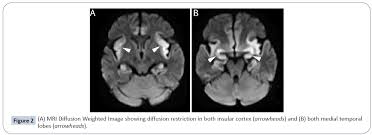

In children older than 3 months and in adults brain biopsy: Herpesviral encephalitis, or herpes simplex encephalitis (hse), is encephalitis due to herpes simplex virus. • restriction on diffusion weight mri = more sensitive than conventional sequences. Misra uk, hashmi aa, kalita j. Diagnostic uncertainty and empirical management in pcr negative encephalitis. It is a severe condition brain mri may show limbic encephalitis (55) or diffuse t2 and dwi hyperintensities in the white matter, associated with restricted diffusion (54). Herpes simplex encephalitis occurs as 2 distinct entities: Mri is the imaging of choice in suspected cases of viral encephalitis, although ct scanning may be used where mri facilities are not available. The patient had initially improved after medical treatment. Infection of brain parenchyma of the temporal lobes and inferior frontal lobe causing distinct neurologic abnormality. Dhawan a, kecskes z, jyoti r, kent al. Associated with hsv encephalitis (strong evidence). In addition, because of the involvement of the.

It is a severe condition brain mri may show limbic encephalitis (55) or diffuse t2 and dwi hyperintensities in the white matter, associated with restricted diffusion (54). Brain mri—increased t2 signal intensity in frontotemporal region → viral (hsv) encephalitis. Associated with hsv encephalitis (strong evidence). Provided cranial imaging has excluded any contraindications such as a space occupying lesion or severe cerebral oedema and brain shift, a csf. Having said that, mri with contrast is considered the most sensitive imaging modality, and findings are present in over half of individuals 8. In addition, because of the involvement of the. We performed volumetric measurements of the left and right temporal lobes and of cerebral oedema. Herpes simplex encephalitis occurs as 2 distinct entities: The study analysed serially acquired magnetic resonance images (mri), of patients with acute hsv encephalitis who had neuroimaging repeated within four weeks of the first scan. Pregnancy the most common cause of encephalitis in newborns is vaginal delivery from a mother who is infected with herpes simplex virus 2 (hsv 2). There is no particular age, sex, or seasonal predilection. Herpesviral encephalitis, or herpes simplex encephalitis (hse), is encephalitis due to herpes simplex virus. Severe infection, particularly untreated herpes simplex virus (hsv) encephalitis, can cause brain hemorrhagic necrosis.

Alpha coma in japanese encephalitis. Herpes simplex encephalitis occurs as 2 distinct entities: Brain mri—increased t2 signal intensity in frontotemporal region → viral (hsv) encephalitis. A case of granulomatous hsv encephalitis: Encephalitis caused by hsv type 1 is rare but can result in significant brain damage or death. Contrast enhancement is uncommon during the first week of the disease. The study analysed serially acquired magnetic resonance images (mri), of patients with. Its symptoms are fever, confusion, coma, and seizures. Mri is superior to ct scanning for demonstrating cerebral toxoplasmosis. Brain mri is shown in fig. Having said that, mri with contrast is considered the most sensitive imaging modality, and findings are present in over half of individuals 8. Associated with hsv encephalitis (strong evidence). There is no particular age, sex, or seasonal predilection.